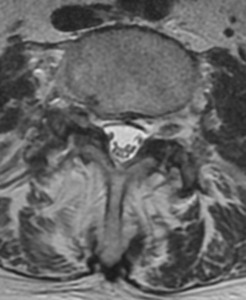

Her MRI images are presented in table 2 and figures 1 and 2. They demonstrate the presence of a number of findings.